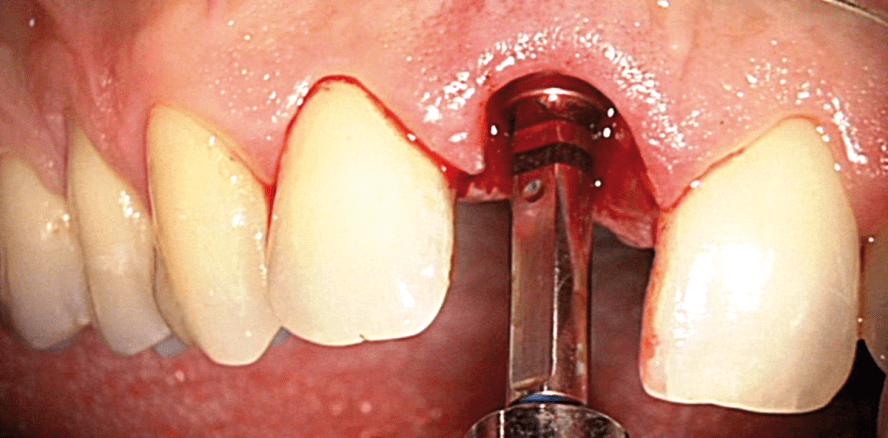

Der Zahn wurde schonend und möglichst atraumatisch extrahiert, um den dünnen bukkalen Knochen zu erhalten (Abb. 7). Nach der Aufbereitung des Implantatbetts gemäß dem Bohrprotokoll des Herstellers wurde ein konisches Implantat mit abgeschrägter Implantatschulter (OsseoSpeed Profile EV, Dentsply Sirona Implants) und 4,8 mm Durchmesser inseriert (Abb. 8–11). Abbildung 11 zeigt, wie die abgeschrägte Implantatschulter dem natürlichen Niveauunterschied zwischen palatinal und fazial entspricht, mit dem palatinalen Knochenniveau abschließt und die periimplantäre Gewebekontur zirkulär unterstützt. Das Implantat wurde palatinal inseriert, die vestibulär entstandene Lücke mit autologem Knochen vom Kieferwinkel augmentiert, um die bukkale Knochenresorption zu mindern (Abb. 12). In das Implantat wurde ein Abformpfosten eingeschraubt und mit einem dual härtenden Composite mit der OP-Schablone verblockt, um die Position des Implantats auf das Meistermodell zu übertragen (Abb. 13). Nach Registrierung der Implantatposition wurde eine Augmentation des fazialen Weichgewebes in Tunneltechnik vorgenommen, um die faziale Rezession zu decken (Abb. 14). Durch das Bindegewebstransplantat kommt es sowohl zu einer Verdickung als auch einer Koronalverschiebung der periimplantären Mukosa. Die Rezession wird beseitigt und so eine gute Voraussetzung für ein dauerhaftes stabiles ästhetisches Ergebnis geschaffen. Als Nächstes folgte die faziale Knochenaugmentation ohne Lappenbildung mit Knochenpartikeln aus dem Unterkiefer (Abb. 15). Um zu verhindern, dass Knochenpartikel in das Innere des Implantats gelangen, wurde übergangsweise ein schmales Healing-Abutment (UniAbutment EV) eingebracht. Dies verhindert, dass Knochenspänchen ins Implantatinnere rutschen. Der Zahntechniker erstellte eine verschraubte provisorische Sofortversorgung, die am Tag der Implantatinsertion angefertigt und eingesetzt wurde. Die provisorische Krone wurde mittels einem Glasfaserband und einem fließfähigen Composite mit den angrenzenden Zähnen verblockt (Abb. 16 und 17). Die Verblockung wurde nach acht Wochen entfernt. Abbildung 18 und 19 zeigen die verbesserte Weichgewebssituation vor und nach der Neukonturierung durch die provisorische Versorgung.